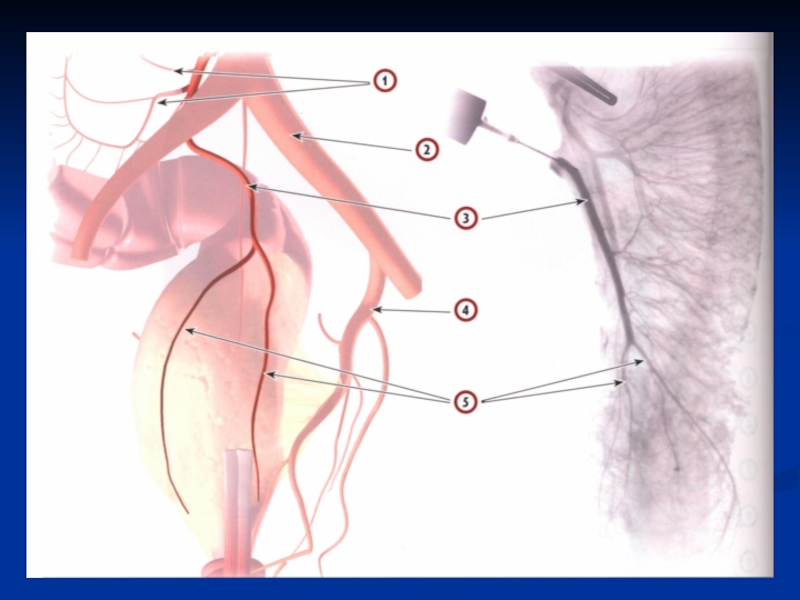

Слайд 11Пути метастазирования

Лимфогенный (30%) (регионарные лимфатические узлы (параколические, вдоль a. ileocolica,

a.colica dextra, a.colica media, a.colica sinistra, a. mesenterica inferior), отдаленные

лимфоузлы (парааортальные);

Гематогенный (50%) – в печень, легкие, кости, ПЖ;

Имплантационный (20%).

Слайд 12Лимфогенное метастазирование

Лимфогенное метастазирование

Слайд 14Лимфогенное метастазирование